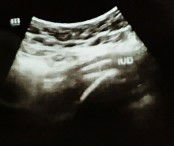

20 weeks 2 hari, belum terasa pergerakan

Bun, kandungan ku sudah 20 minggu 2 hari. Tapi ukuran perut gak begitu banyak berubah, dan aku gak ngerasa pergerakan janin yg signifikan. Waktu lalu pas aku hamil anak ke 3 di umur 4 bulan udah kerasa pergerakan nya, perut juga keliatan berubah.. Itu gimana ya bun? Adakah info atau saran?#seriusnanya